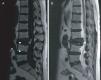

Reconstrucción sagital por TC en la que se aprecia un colapso casi completo del cuerpo vertebral de L3 con desplazamiento del muro posterior condicionando una estenosis del canal medular, e imagen de vacío intravertebral (flecha blanca). También se objetiva signo del vacío discal en L2-L3 y L3-L4 (puntas de flecha).

La ON es una entidad poco frecuente que se caracteriza por un colapso vertebral y la presencia del FVI1,2. La locación más común es la unión tóraco-lumbar. Suele presentarse en pacientes de edad avanzada y/o con osteoporosis previa. De hecho, en la actualidad siguen existiendo discrepancias en cuanto a si se trata de una osteonecrosis vertebral que subsecuentemente se colapsa, o una fractura vertebral por osteoporosis que condiciona un cierto grado de isquemia ósea local (la fractura produciría una compactación de la esponjosa que dificultaría el flujo sanguíneo). Otros factores relacionados con la aparición de esta entidad son el abuso de alcohol, un traumatismo de poca intensidad, la radioterapia o el tratamiento prolongado con glucocorticoides1. Aunque existe una mayor afectación de la parte anterior de la vértebra que de la posterior (lo cual coincide con la zona de vascularización más alterada), en algunos casos pueden aparecen complicaciones neurológicas por desplazamiento del muro posterior condicionando una estenosis del canal medular.